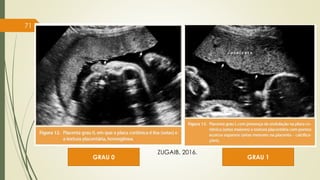

MATURIDADE DA PLACENTA – GRAU PLACENTÁRIO

GRAUS PLACENTÁRIOS

GRAU 0 Presença de placa coriônica lisa e textura placentária

homogênea.

GRAU I Presença de ondulação na placa coriônica e textura placentária

com pontos ecoicos esparsos.

GRAU II Presença de imagens hiperecóicas lineares na placa basal

(calcificações).

GRAU III Presença de calcificações em todo o contorno dos cotilédones.

70

CLASSIFICAÇÃO DE GRANNUM, BERKIWITZ, HOBBINS (1979)

GRAU 0 GRAU 1

71

ZUGAIB, 2016.

GRAU 2 GRAU 3

72

Grau III < 34 semanas - diminuição do volume de LA e sofrimento fetal;

Após 37 semanas de gestação, aproximadamente 60% das placentas são de grau II; 20%,

de grau III; e 20%, de grau I (HC-FMUSP).